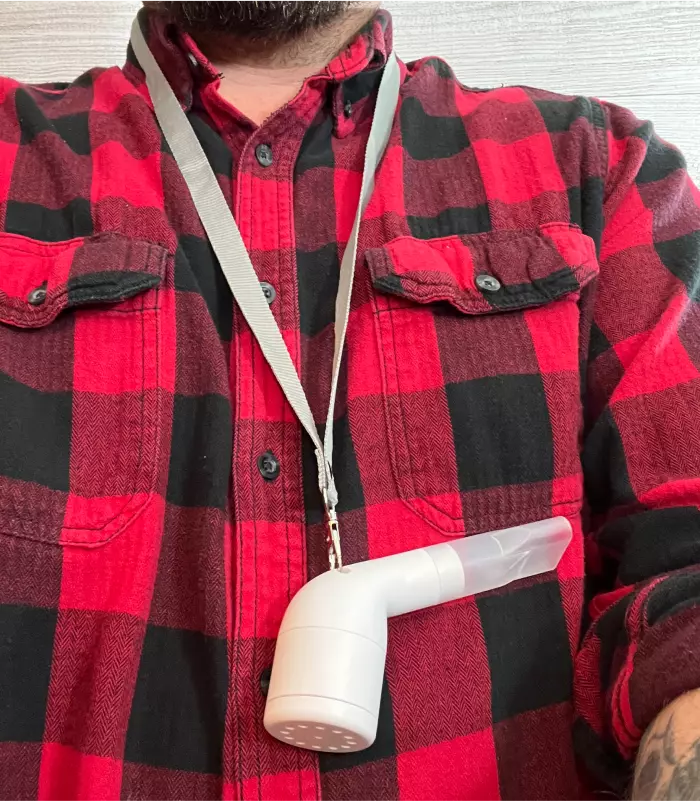

This GENIUS new device gives your lungs a ”Breathing Workout'” to make them stronger, clearer, and healthier

Looking for a way to boost your lung health, improve your breathing, and shift mucus obstructing your airways? Then this breakthrough new invention is perfect for you!

RespiraFix is a medication-free, easy-to-use device that strengthens and clears your lungs. It achieves this by providing a "breathing workout" that helps to reduce mucus buildup and improves overall lung function. It’s especially beneficial for anyone suffering from long-term respiratory illnesses like asthma, COPD, or emphysema.

RespiraFix helps you to dislodge and expel mucus while increasing your lung capacity. And it does this via cutting-edge, scientifically proven OPEP techniques.